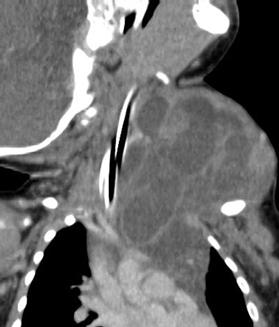

頚部リンパ管腫に対して硬化治療が奏功した一例

胎児超音波検査で頚部リンパ管腫を指摘されていた症例で、生後4か月時に病変が急速に増大して、呼吸困難で受診、外来で緊急気管挿管・緊急入院となりましたが、透視下に硬化療法を行ったところ、嚢胞性病変のほとんどが潰れて、治療後は腫れなくなり、元気に過ごしています。

圧迫して呼吸促迫になったため緊急気管挿管

(左頚部から縦隔に広がる病変)

病変内に注入し、透視で病変への広がりを

リアルタイムに確認。CT画像で指摘された

病変に一致して薬剤が広がった。

頚部の腫瘤はほとんど目立たなくなった。